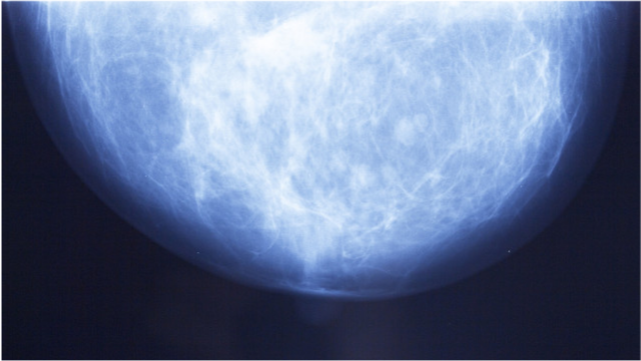

经常有女性朋友会问:“我做了乳腺钼靶 , 报告提示有钙化 , 是不是得乳腺癌了?”

接下来 , 我们讲一讲乳腺内的钙化灶是怎么发生、怎么检查 , 以及哪些钙化灶是乳腺癌或者可疑乳腺癌 。

这些钙化灶 , 我们的肉眼看不到 , 手摸不到 , 病人也常没有任何不适 。 很多时候 , 超声或MRI都发现不了 , 而乳腺钼靶是发现钙化灶最好的检查 。